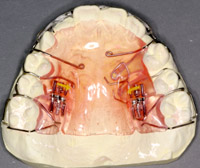

この時期の矯正装置は、ほとんど取りはずせる装置 床矯正装置ですが、一部には固定式や頭などにかぶるものもあります。

床矯正装置